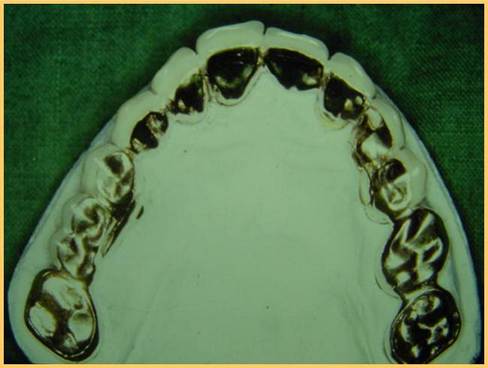

噛み合わせの器械につけて、ワックスで形を作り、診断をしたり、仮の歯を作ります。

リーゲルのレバーがかかる部分です。

下のリーゲルテレスコープの途中経過。